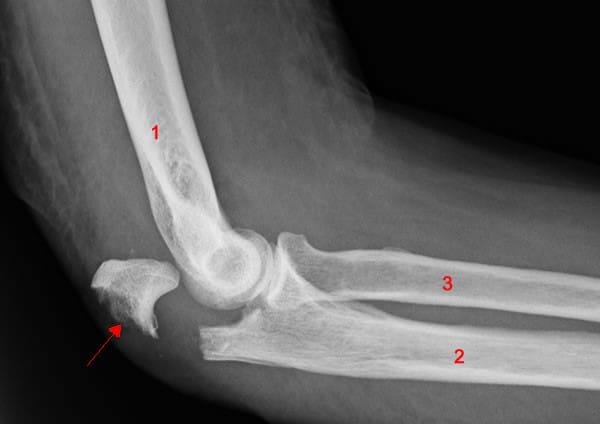

If the ikkyo technique is then applied martially, the result looks like the image below. There is a fracture of the olecranon, possibly displacement of the radius (3) and ulna (2), or even fracture of the humerus (1):

None of this sounds very attractive, but it's important to understand that this is what the ikkyo technique is designed for, not to gently bring an opponent to the ground. If you take uke to the ground, it's only because it's obviously not possible to break your training partner's arm.